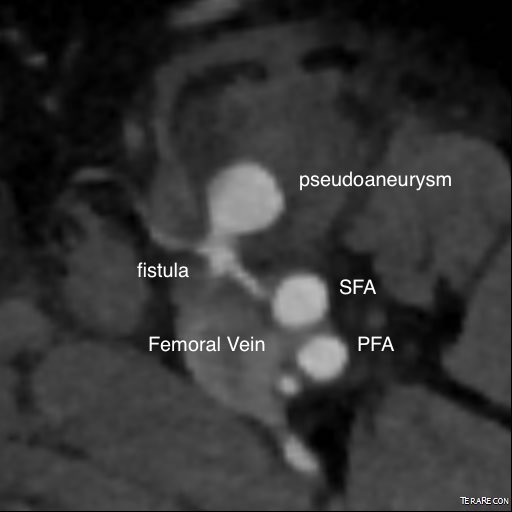

The patient had a 8cm sphere shaped aneurysm arising in the transdiagphragmatic aorta, leaking into the right pleural cavity.

The patient was otherwise a healthy middle aged man with risk factors of smoking and hypertension. The centerline reconstructions showed the thoracic aorta above the aneurysm to be around 20mm in diameter and same below, with the celiac axis and superior mesenteric artery in the potential seal zone of a stent graft. The only plaque seen was around the level of the renal arteries and was focal and calcified. Looking at the list I had made as a comment to the Linked-In post, I realized that I really only had one viable option.

Open repair, usually the most expeditious option, was made challenging by the right hemothorax, making a left thoracotomy hazardous if the lung had to be deflated. Cardiopulmonary bypass would have to be arranged for, and that adds a metabolic hit that greatly raises the stakes. Of the endovascular solutions, the only viable option was TEVAR to exclude the rupture and debranching of the celiac axis and superior mesenteric artery. To those who would advocate for parallel grafts, there was no room in the normal 20mm diameter aorta. And branch systems for rupture are some time in the future. Also, the patient was becoming hypotensive. So the planned operation was first TEVAR to stop the bleeding, and then open surgical debranching. A hybrid repair.

As seen below, the graft excluded the celiac and SMA. Late in the phase of the final aortogram (second panel) there was an endoleak that persisteed despite multiple ballooning. The timing suggested the intercostals and phrenic vessels contributed to a type II endoleak, but it was concerning.